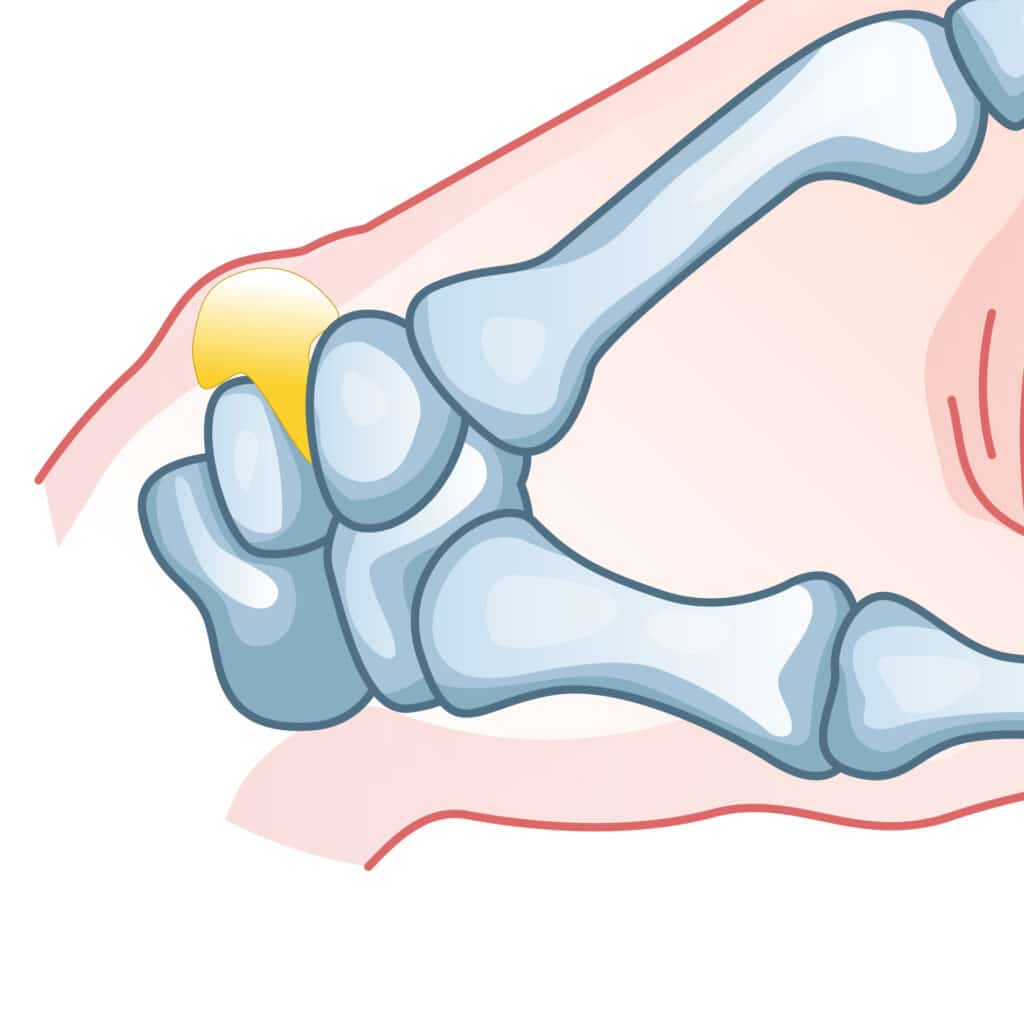

Joint fractures of the fingers